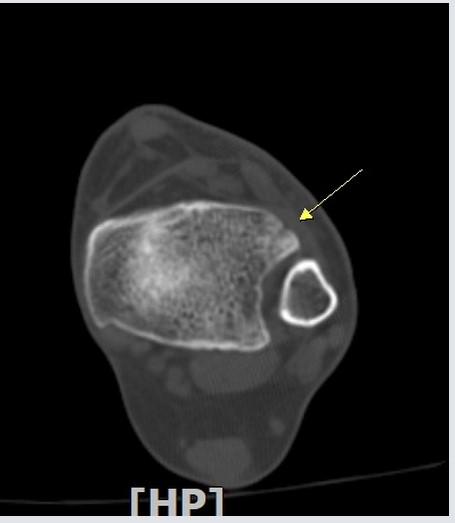

¾Õ°æ°ñºñ°ñÀδë Á¾´Ü¸é°Ë»ç¿¡¼­ °æ°ñºñ°ñÀδëÀÇ  Àú¿¡ÄÚ  ºÎÁ¾ ¹× ÀδëºÎÂøºÎ °æ°ñÀÇ

°ß¿­°ñÀýÀÌ  °üÂûµÊ(»çÁø 2, 3, 4)

°Ë Ç» ÅÍ ÃÔ ¿µ : ÃÊÀ½ÆÄ°Ë»ç¿¡¼­ °üÂûµÇ´Â  °Íº¸´Ù  ºñ±³Àû  Å«  °ñÆíÀÌ °üÂûµÊ(»çÁø 8, 9, 10).